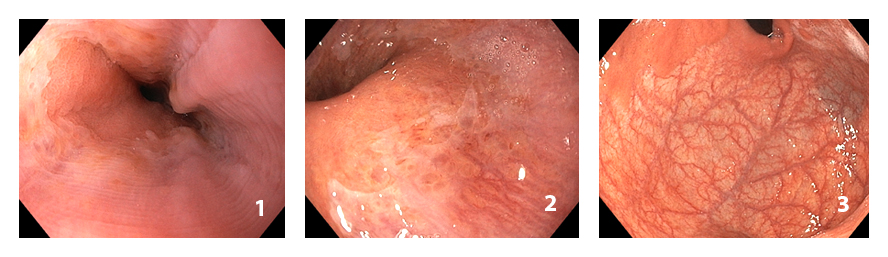

Фото 1,2 - микрокисты кардиоэзофагеального перехода, фото 3 - отсутствие собирательных венул слизистой области дна желудка

Первый признак — белые точки на слизистой оболочке двенадцатиперстной кишки. Он вовсе не специфичен для аутоиммунного гастрита, то есть встречается и при других состояниях и болезнях человека, но он необходим при постановке диагноза. Белые точки появляются при снижении кислотности желудка, так как и ее изменение (как снижение, так и повышение) вызывает бактериальный рост, в результате лимфатические сосуды расширяются и при эндоскопическом исследовании это проявляется в виде белых точек.

Второй признак — микрокисты кардиоэзофагеального перехода (место соединения желудка с пищеводом). По словам Сигаевой, их можно увидеть при проведении эндоскопического исследования даже при обычном свете и без увеличения.

Третий признак — исчезновение собирательных венул в проксимальных отделах желудка, в его верхней трети.

«Собирательные венулы — это показатель того, что кислотопродуцирующая слизистая оболочка существует. А если при аутоимунном гастрите она начинает пропадать, то происходит это в области дна желудка. Эту область эндоскописты при исследовании часто пропускают. Иногда за атрофию можно принять бледность слизистой оболочки, но при более внимательном осмотре и приближении видно, что собирательные сосуды есть, несмотря на бледность, а при аутоиммунном гастрите они отсутствуют, мы видим пустые пятна», — рассказала наша собеседница.